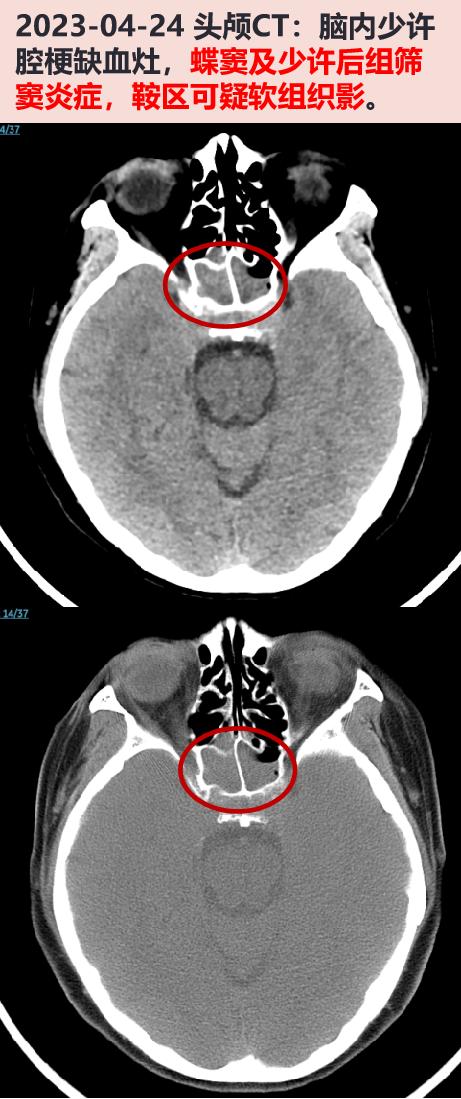

2023-05-05 头颅mri增强:脑内少许腔隙性缺血灶,蝶窦炎症